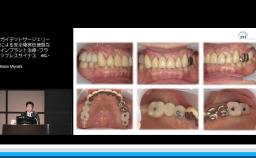

Keizo Miyoshi

Setagaya-ku,, Japan